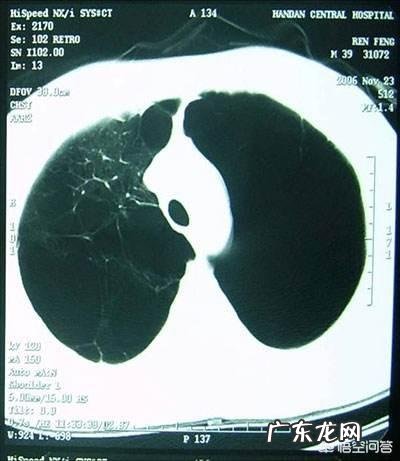

文章插图